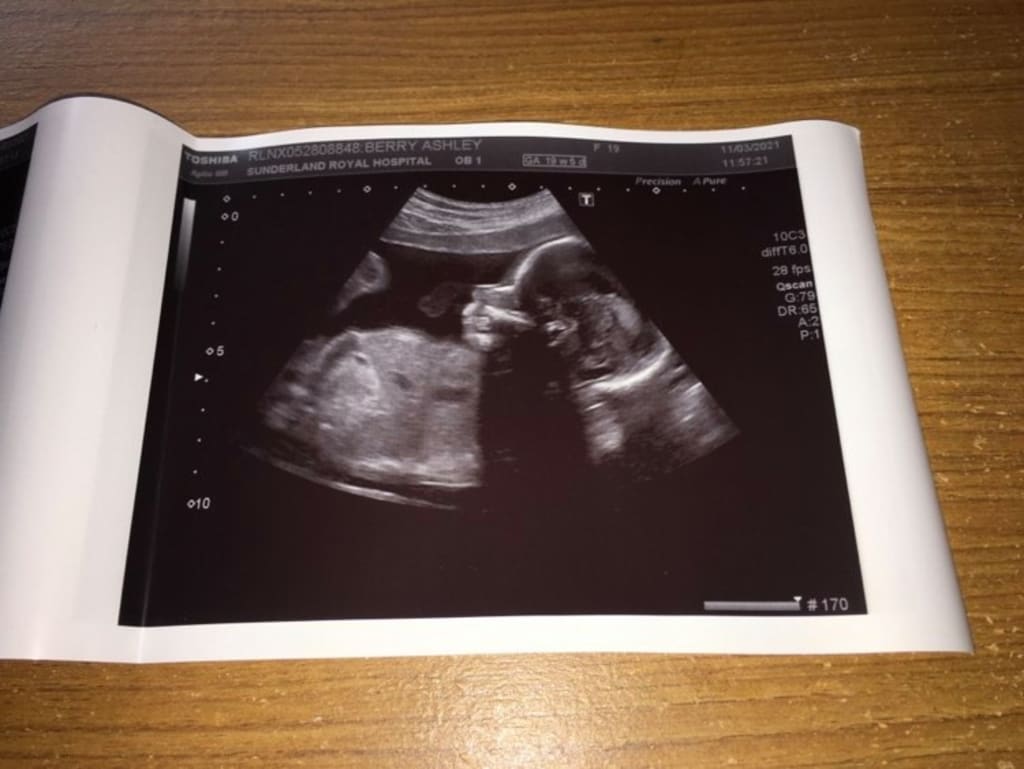

In August 2020 I de-transitioned after living as Tyler (he/him) for over 3 years. November 2020 rolled around and me and my partner found out that i was 2-3 weeks pregnant. This for us was 100% a planned pregnancy as we have both always wanted a family but it struck a bit sooner than expected. I stopped my hormone replacement therapy (HRT) in August and by calculations I fell pregnant in October. This would have to mean that I began ovulating again within 2 months after stopping my testosterone shots. A lot of people say im lucky to have gotten so pregnant so quickly as some people spend years trying to get pregnant but for us it was definitely a shock.

I am now just over 23 weeks pregnant and I have started to realise that transitioning in the first place and living as Tyler was absolutely the correct decision for me. I am continuing with the pregnancy as i will always say to everyone that i am over the moon to be pregnant and it is one of the best most rewarding feelings ever. However after i have given birth i will be restarting my HRT and living back as Tyler again.

Although my family haven't been the most supportive through this massive change in my life, I have however had a lot of support elsewhere. Hospitals have been so understanding of my past and have helped put me and my partner at ease with the whole process especially considering I had testosterone going through my body for a year. We got concerned that there would be complications but the midwives at our old flat and our new house have been outstanding.